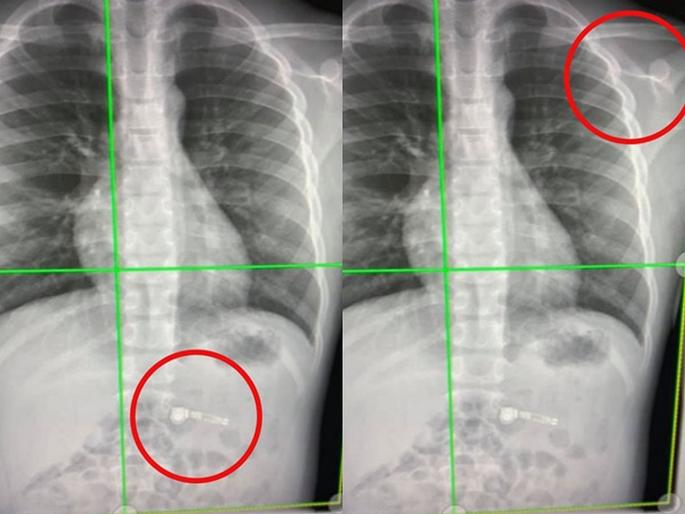

डॉक्टरांनी मुलाचा एक्स-रे काढला तेव्हा दोन्ही एअरपॉड्स त्याच्या पोटात दिसले. डॉक्टर म्हणाले की, एअरपॉड्स आपोआप नॅच्युरल प्रोसेसने बाहेर येतील. मुलाची आई कियाराने सांगितले की, त्यांचा मुलगा फारच मस्तीखोर आहे. मस्ती-मस्तीमधेच त्याने एअरपॉड्स गिळले. पण त्या पलिकडे जाऊन प्रश्न हाही उभा राहतो की, ७ वर्षाच्या मुलाला कुणी एअरपॉड्स गिफ्ट देतं का?